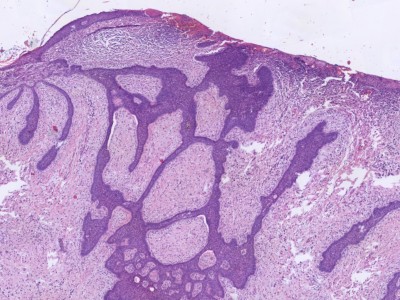

![Fibroepithelioma (Pinkus tumor) (click on photo to enlarge) [source: www.huidziekten.nl] Fibroepithelioma (Pinkus tumor)](../../../images/pinkus-tumor-1z.jpg) |

| fibroepithelioma

(Pinkus) |

PA:

De histologie toont dunne anastomoserende strengen basaloide keratinocyten (soms

squameuze differentiatie) die ruimten gevuld met stroma omlijsten als 'kozijnen

rond een ruit'. Driedimensionaal gaat het om een honingraat vormige of sponsachtig

opgebouwde tumor die begint in de papillaire dermis en die bij groei de papillaire

dermis opblaast en een gesteelde laesie vormt. In de ruimten groeien soms structuren

die lijken op haarzakjes in vroege embryonale ontwikkeling, die 'follicular

germ-like structures' worden genoemd. Immunokleuringen tonen vaak (85%) cytokeratin

20 (CK20, Merkel cellen) en BCL-2 (proto-oncogen), soms androgeen receptoren,

soms zwakke aankleuring p53 of proliferatie marker Ki-67. Sommige pathologen

beschouwen het als een gefenestreerde variant van een trichoblastoom. Het niet-aggresieve

gedrag past daar goed bij. Cysteuze varianten komen voor.